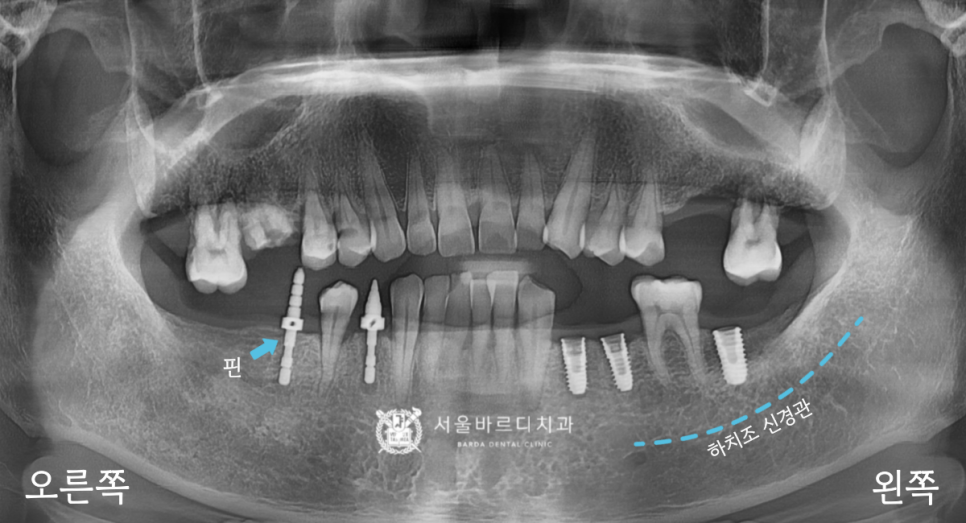

가이드 장치를 끼운 상태에서

해당 부위만 길을 만들어서 픽스처를 심은 덕분에

하치조 신경관의 손상 없이 바르게 심겼네요.

20230223

만약에 신경관을 건드리게 된다면

입술이나 볼에 마취가 안 풀린 것처럼

둔한 감각이 남아있어서 신경이 돌아올 때까지

별도의 치료가 필요하게 되는데요.

이를 막기 위해서 CT를 분석하여

미리 계획해둔 자리에 심은 덕분에

오른쪽도 손상 없이 안전하게 들어갔습니다.